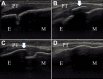

Methods: The study participants were junior baseball players who participated in a medical checkup in 2020. We included knees in the apophyseal stage evaluated using ultrasonography, and classified them into the bursitis and no-bursitis groups using color-enhanced Doppler ultrasonography. We also investigated bone lesions of the tibial tuberosity, determined by fragmentation of the bone and irregularity of the ossification center. Demographic data, practice duration, pressure pain on tuberosity, pain while playing baseball (visual analog scale), heel-buttock distance (HBD), straight-leg raise angle, and range of hip internal and external rotation were evaluated. Group comparisons were performed using the Mann-Whitney U test and Fisher exact test, and a logistic regression analysis was performed.